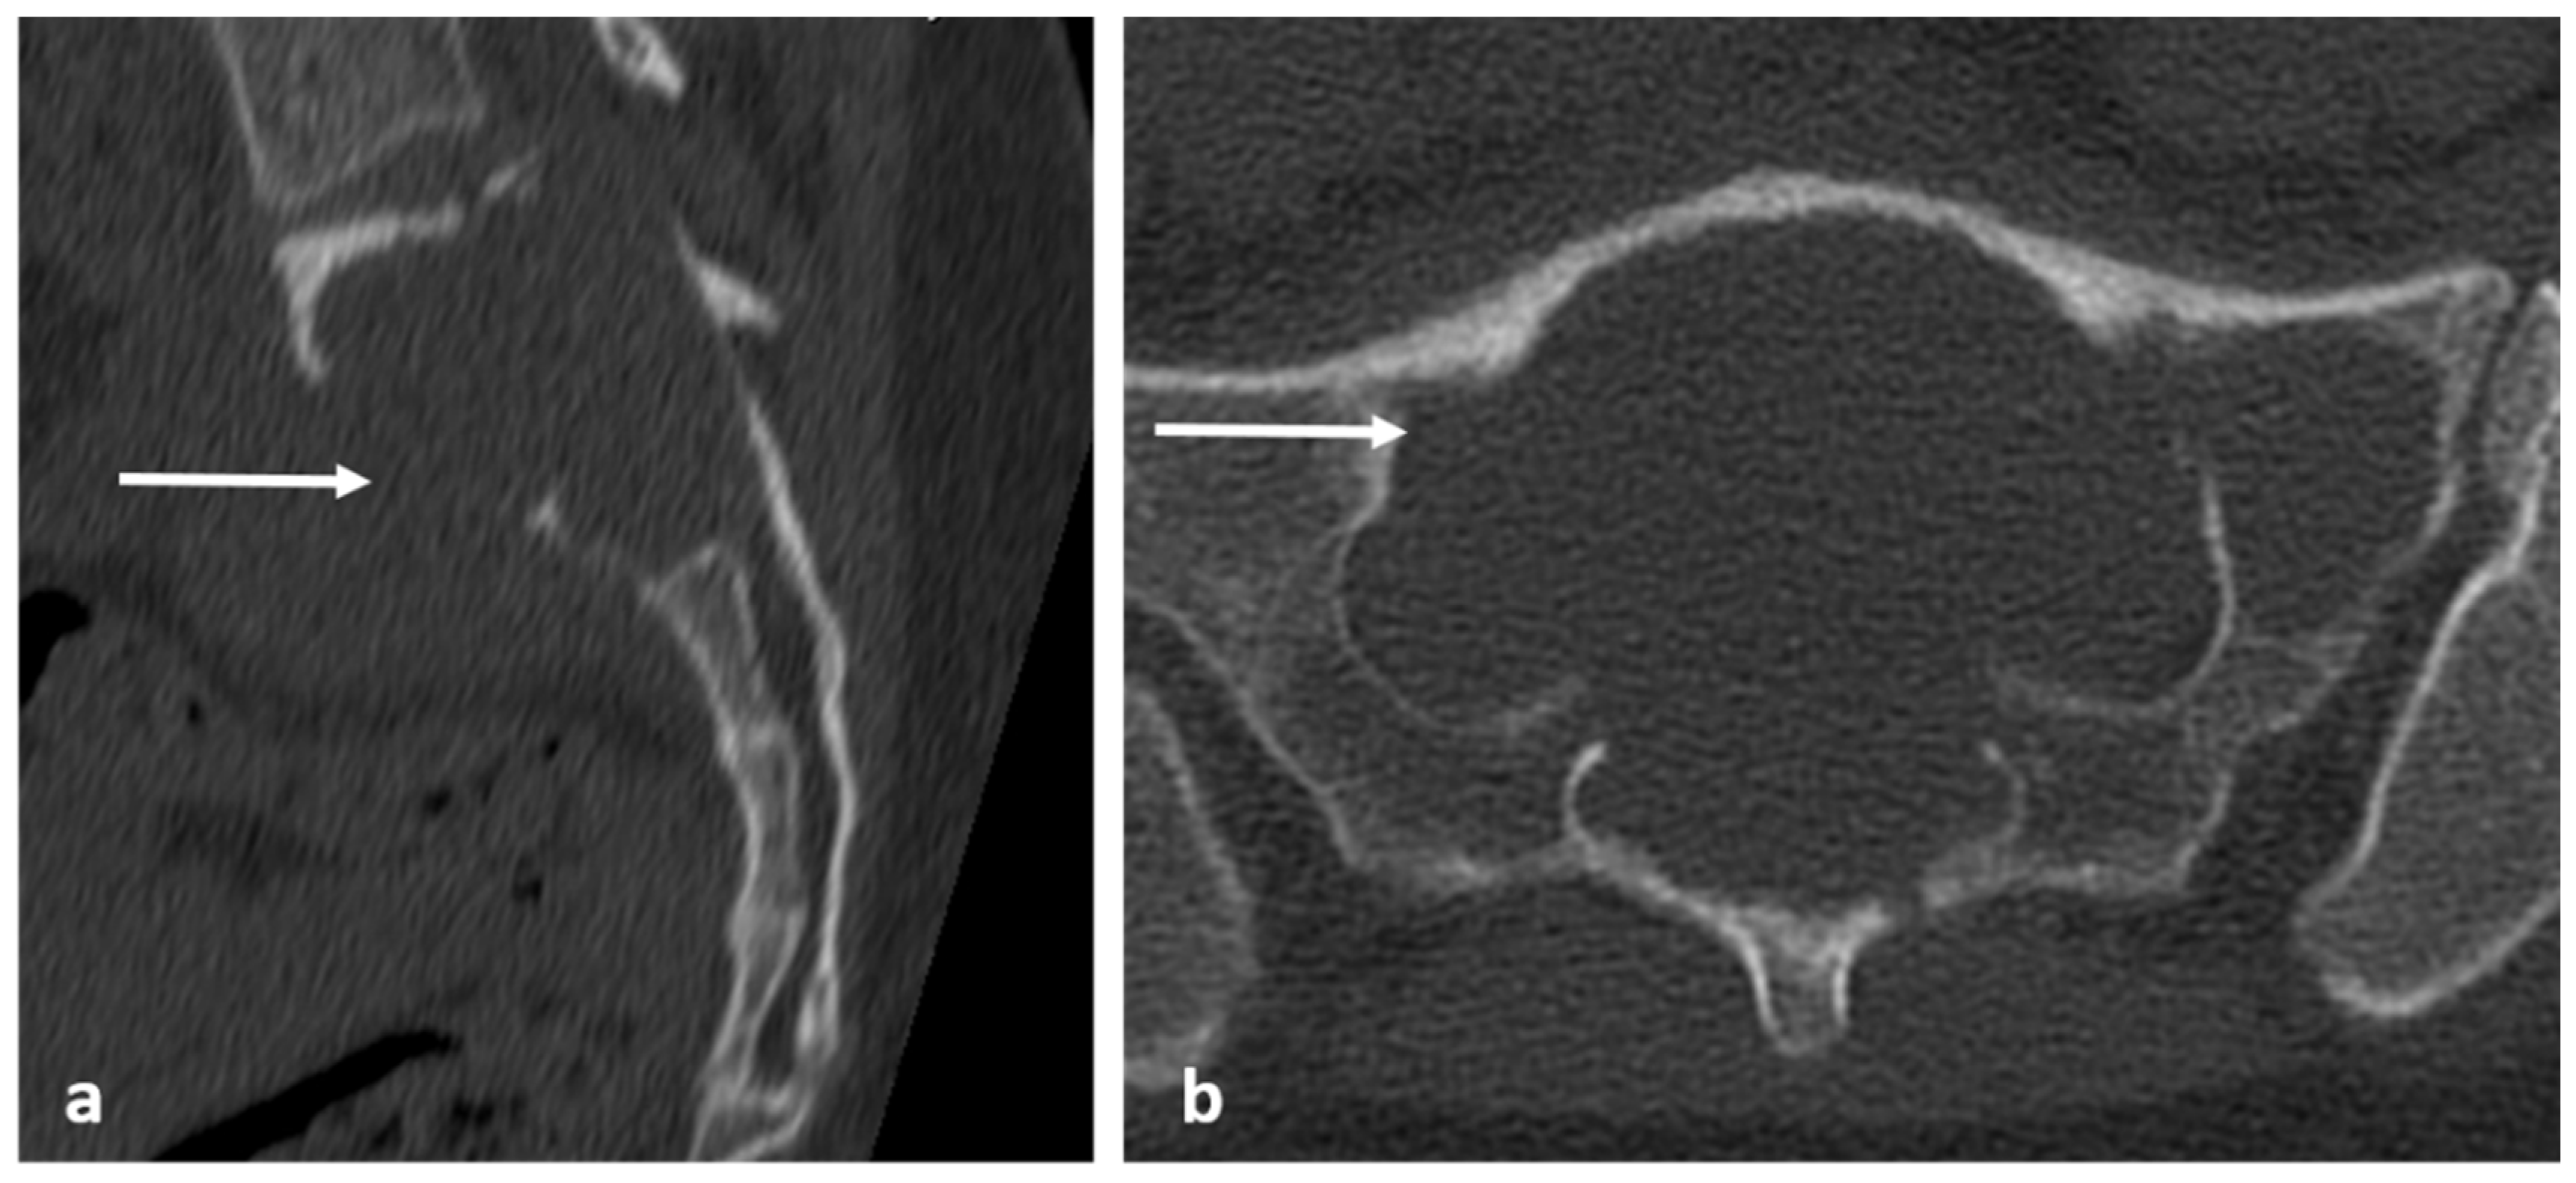

3.10. Notochordal Tumours

| Benign notochordal tumour | Midline lesion in the body. Sclerosis or trabecular thickening typically, but lysis can be present. | Low T1 and high T2 signal. No enhancement. |